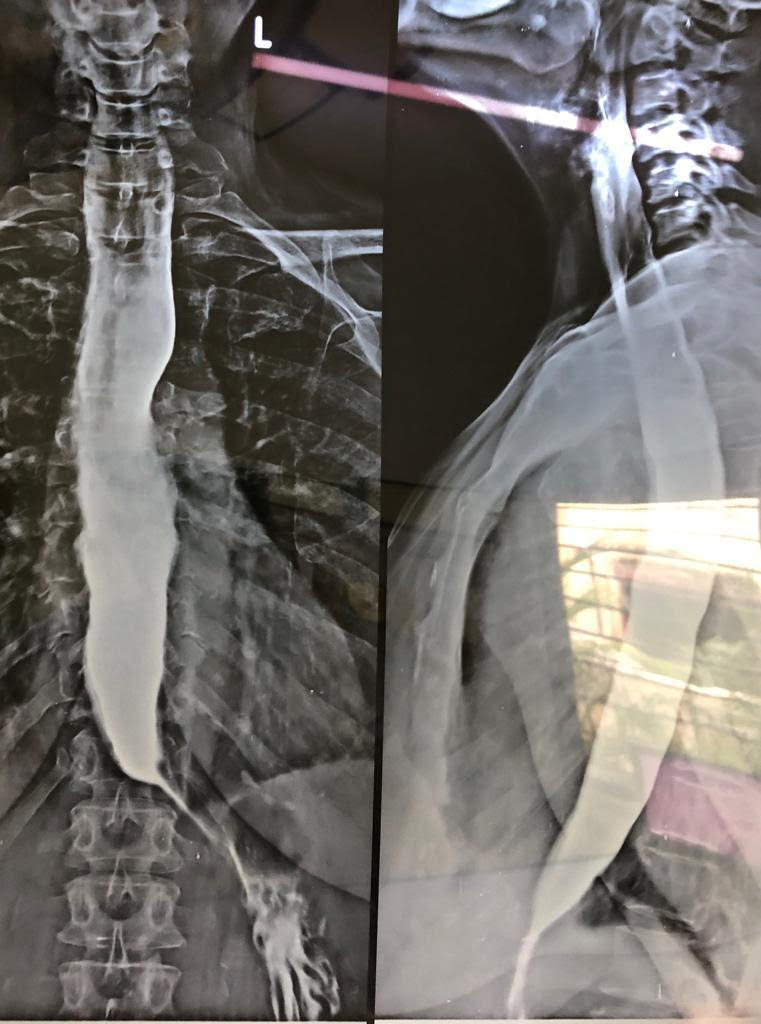

60 year short statured female with copd had dysphagia EGD Scopy confirmed a aperistaltic esophagus with classical ‘give way’ at the esophago gastric junction. Barium swallow and HR manometry done.